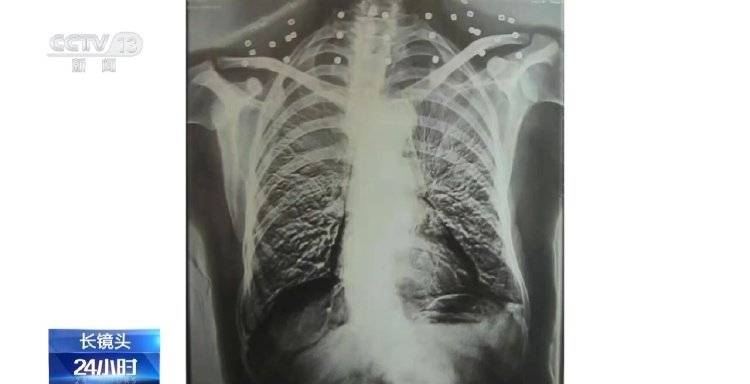

央视新闻客户端消息,这张CT照片是82岁吴以先老人的CT照,当初拍片时,医生说,“老先生,您要把项链取下来再做CT。”

吴以先老人跟医生说,“可我从来没戴过项链,怎么会有项链呢?你看会不会是弹片?”自此,引出了一段老人不平凡的往事。

二十年前,吴以先老人做CT检查时发现,他的颈部有许多弹片,医生当时把弹片误认为是老人戴的项链,于是提醒他要把项链取下来再做检查。

这是吴以先老人体内的33颗弹片,也是老人摘不下来的“项链”。